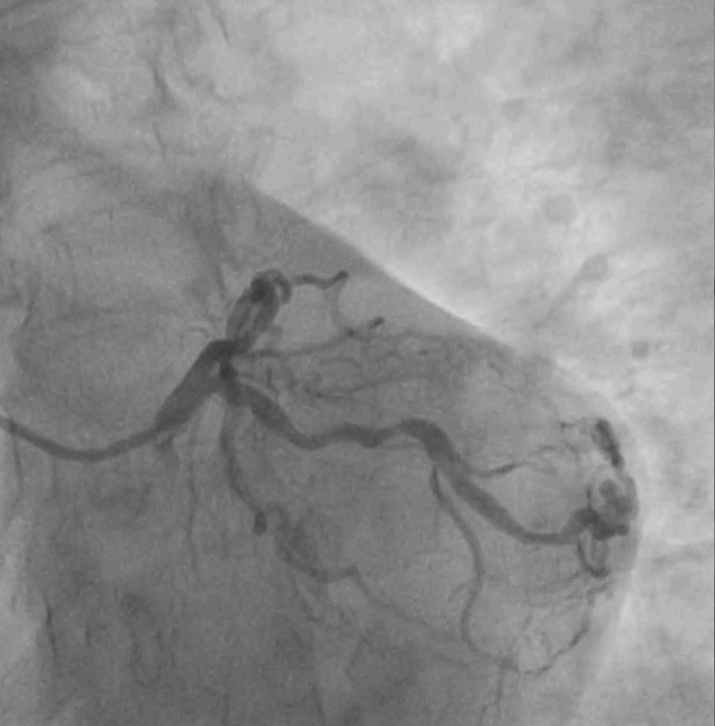

63 An old female patient presented with unstable angina for 6 months, k/c/o HTN, TYPE II DM, 2DECHO S/O LVEF 45% WITH INFERIOR WALL HYPOKINESIA WITH PRESERVED WALL THICKNESS., CAG S/O TVD WITH RCA CTO

CAG S/O TRIPLE VESSEL DISEASE, WITH RCA CTO FILLING RETROGATELY. ADVICE CABG BUT PATIENT IS NOT WILLING FOR CABG

PTCA with Retrograde Rendezvous for Chronic Total Occlusion (CTO)An individual with a stubborn Chronic Total Occlusion (CTO) in the RCA (Right Coronary Artery) initially underwent a failed antegrade percutaneous transluminal coronary angioplasty (PTCA). Despite multiple wire attempts (e.g., CROSSIT 200, PILOT 150), the procedure was aborted due to a spiral dissection.A month later, a second attempt was made using a more advanced approach. The steps were as follows:Retrograde Access: The interventional team chose a retrograde approach, navigating a wire and microcatheter through collateral vessels to reach the RCA distal to the blockage.Antegrade Access: Simultaneously, an antegrade wire was advanced from the proximal end of the RCA to the blockage site.Rendezvous: The retrograde and antegrade wires were "kissed" at the site of the CTO. This crucial step, known as the rendezvous technique, allowed the antegrade wire to be precisely guided.Final Crossing: The antegrade wire was then advanced through the antegrade microcatheter, alongside the retrograde wire, finally penetrating the true lumen distal to the CTO.Revascularisation: Once the path was clear, the retrograde wire was removed. The RCA was then successfully revascularized with balloon dilations and the deployment of two stents.